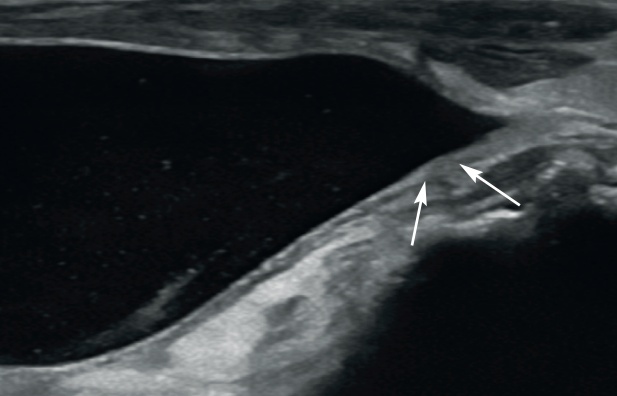

가장 중요한 포인트는 신문(hilus)에서 혈관을 ‘확장 요관’으로 착각하지 말아야 한다는 점입니다. 신동맥과 신정맥도 신문으로 들어오므로 이것을 확장된 요관으로 오인할 수 있습니다. 이때 컬러 도플러가 도움이 됩니다. 혈액은 도플러 신호가 잡히나, 소변은 도플러 신호를 만들 만큼 빠르게 흐르지 않아서 신호가 잡히지 않습니다.